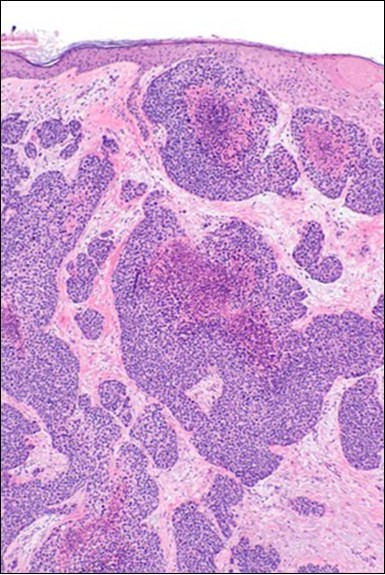

Figure 1.Solid aggregates of tumour cells and duct structures in eccrine porocarcinoma (14).

Solid aggregates of tumour cells and duct structures in eccrine porocarcinoma (14).

Eccrine porocarcinoma is an infiltrative, high grade tumour which is contiguous with superimposed epidermis, depicts a partially lobular architecture and a diameter usually exceeding > 90 millimetres. An endophytic pattern of tumour evolution is elucidated with invasion of deep reticular dermis and subcutaneous tissue 5, 6.

Classically, intra-epidermal and dermal nests of tumour cells exhibiting cellular atypia and enhanced mitotic activity are enunciated. Tumour aggregates articulate well demarcated, enlarged, atypical polygonal cells with indistinct cellular and nuclear outline, nuclear hyperchromasia , irregular nuclei, vesicular or prominent nucleoli and minimal eosinophilic cytoplasm. Polygonal tumour cells can depict central keratinisation 6, 7.

The neoplasm is composed of lobules of aberrant epithelial cells configured in cords with incrimination of the dermis and epidermis.. Malignant cells congregate within the epidermis or infiltrate the dermis, especially in the primary tumour. Tumour cells within tumour aggregates display a well demarcated cellular outline and appear distinct from encompassing squamous cells. Numerous tumour cell clusters demonstrate a cystic lumen. Prominent epidermal acanthosis is discerned on account of tumour cell proliferation 6, 7.

Granular arrangement of malignant cells and intercellular bridges are conspicuous with the demonstration of nuclear atypia, pleomorphism, prominent mitosis and tumour necrosis. A peripheral palisade is discernible within the cellular aggregates. Mitotic figures are common and can be quantified as up to 12 mitosis/ high power field. Tumour differentiation can prominently be of the ductal category with the demonstration of intra-cytoplasmic lumina. Comedo type tumour necrosis is evident along with foci of squamous differentiation The neoplasm is reactive to periodic acid Schiff ‘s (PAS) stain. (Figure 1, Figure 2, Figure 3, Figure 4, Figure 5, Figure 6, Figure 7, Figure 8, Figure 9, Figure 10, Figure 11, Figure 12, Figure 13.